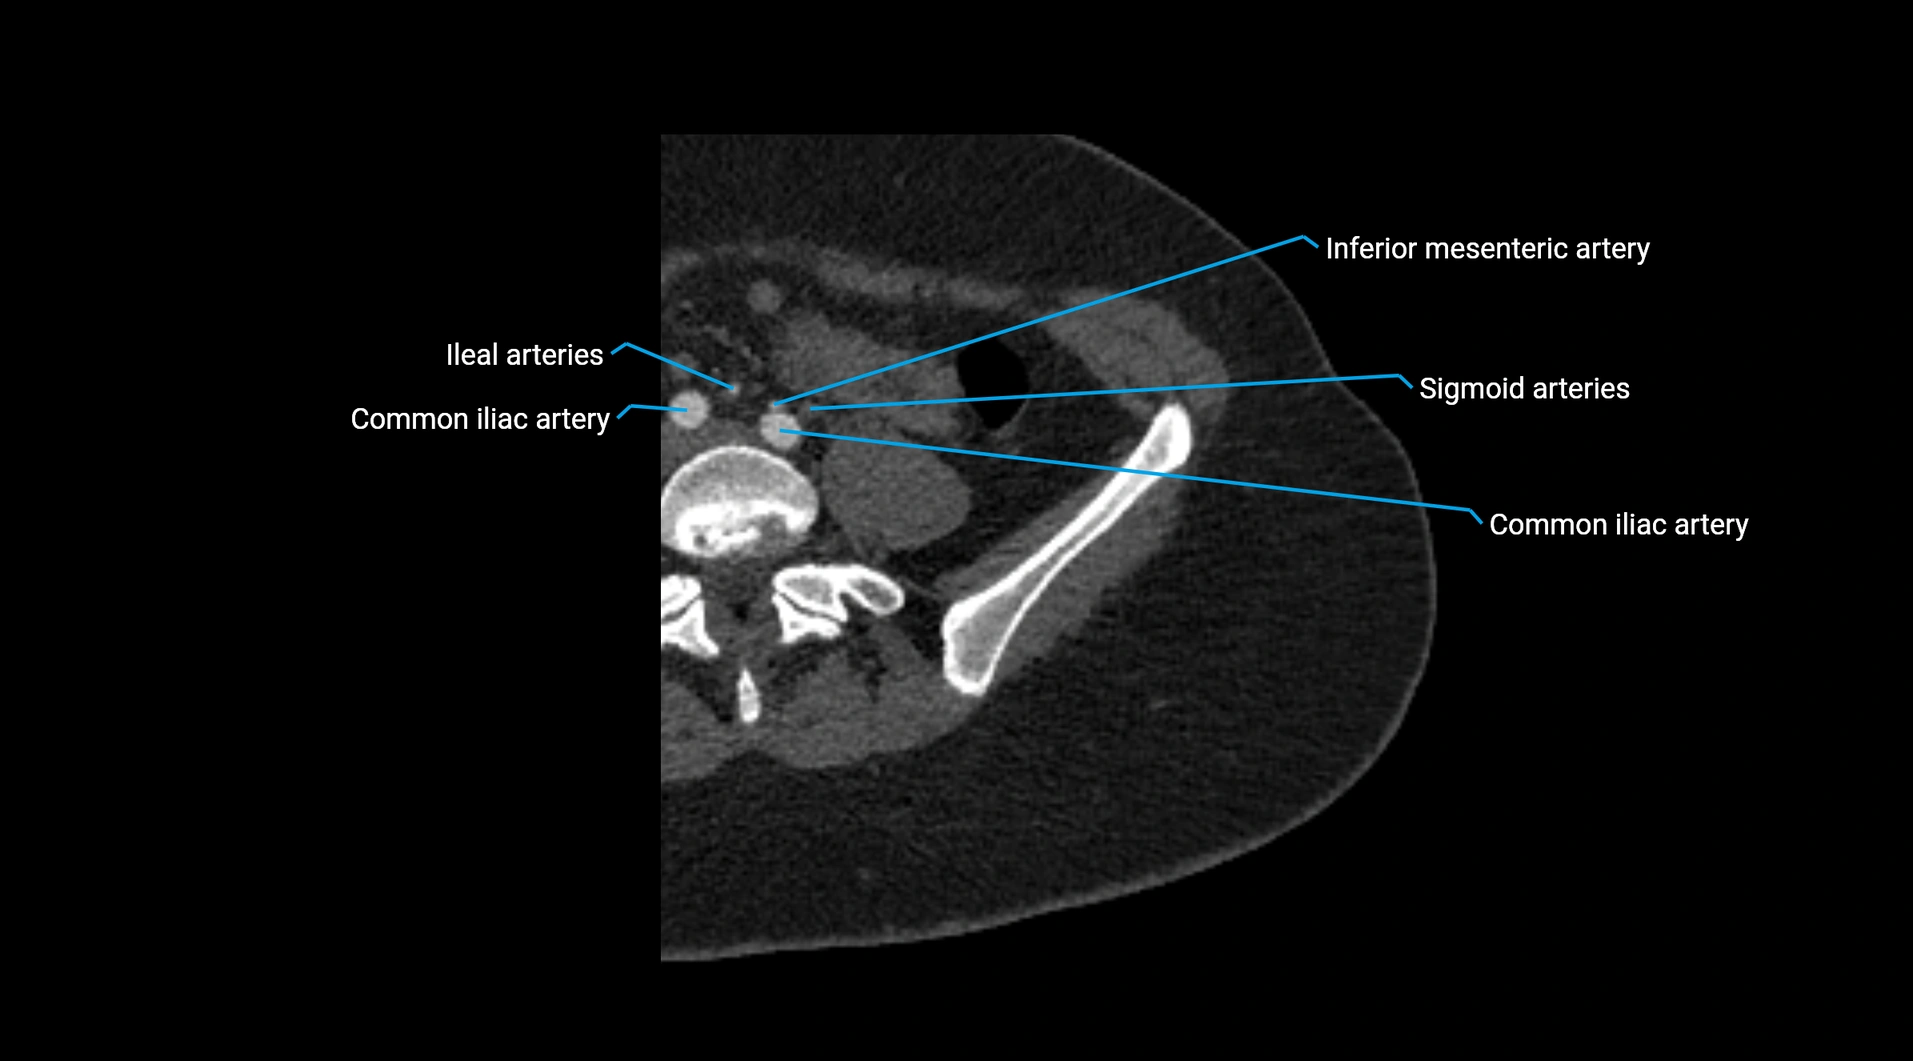

CT images

image